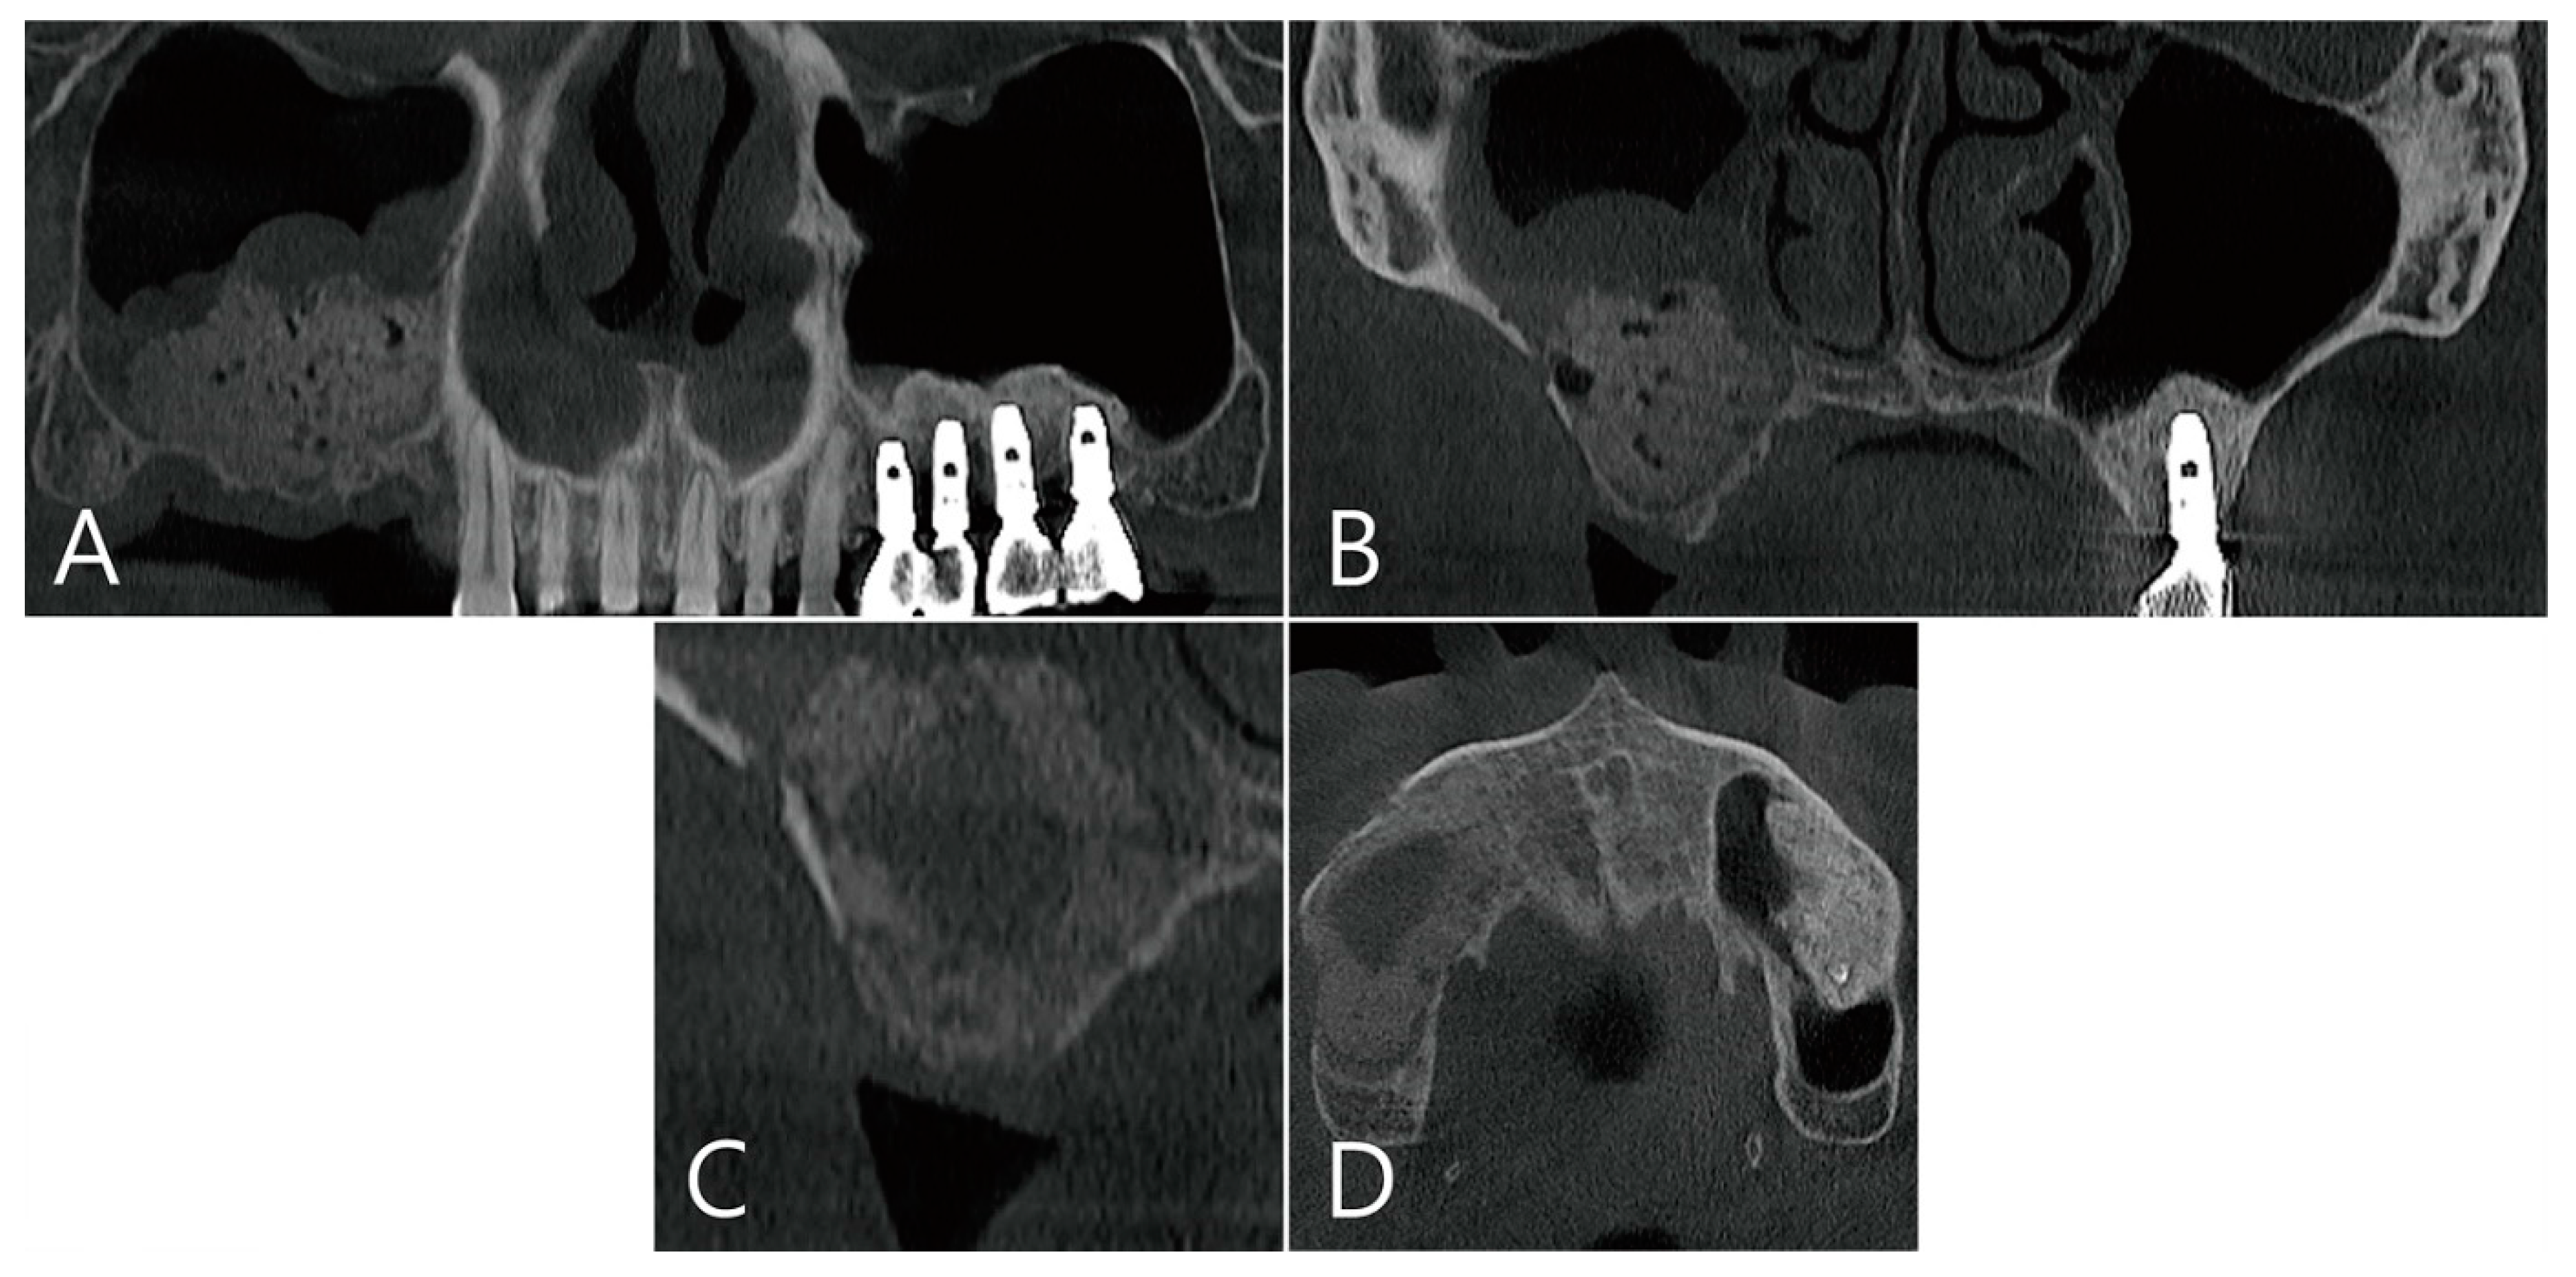

2.5. Case 4

A 75-year-old female who was a non-smoker visited a private clinic to have the implant placed in the edentulous ridge of the maxillary left posterior region (Table 1). This patient was taking antihypertensive and antihyperlipidemic drugs. Preoperative panoramic radiography and CBCT scan were performed. The left maxillary sinus was severely pneumatized and had a minimal residual bone height of 2–4 mm, rendering normal implantation impossible (Figure 10A,B). In the maxillary sinus, membrane thickening was confined to the sinus floor and no sinus pathology was observed in the remaining areas (Figure 10B). Lateral MSA and simultaneous implant placement were planned on the left maxillary sinus.

The coronal image of the CBCT scanned at the #27 implant site was examined. In the image taken immediately after surgery there was no leakage of bone graft particles (Figure 13A), however, a very large grafting void appeared in the image taken one week after surgery (Figure 13B). This grafting void showed a cystic appearance at the implant apex, although its size was reduced on CBCT taken after six months (Figure 13C). On the CBCT taken two years after the grafting void was removed, the grafting void was replaced with new bone (Figure 13D).

Figure 10. Case 4. Preoperative panoramic radiography and CBCT scan were performed: (A) the left maxillary sinus was severely pneumatized and had minimal residual bone height; (B) in the maxillary sinus, membrane thickening was confined to the sinus floor and no sinus pathology was observed in the remaining areas.

Figure 13. The coronal image of the CBCT scanned at the #27 implant site was examined: (A) in the image taken immediately after surgery, there was no leakage of bone graft particles; (B) however, a very large grafting void appeared in the image taken one week after surgery; (C) this grafting void showed a cystic appearance in the implant apex, although its size was reduced on CBCT taken after 6 months; (D) in CBCT taken 2 years after the grafting void was removed, the grafting void was replaced with new bone.